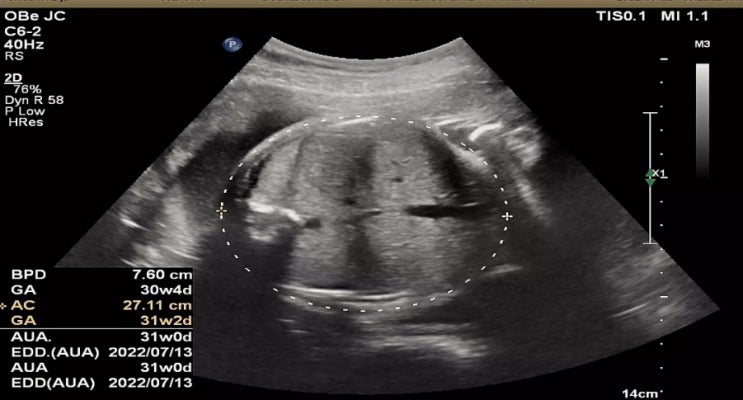

32주 차 정기검진 이제 2주마다 검진이 있어서 30주 차부터 2주 간격으로 병원에 오고 있어요 30주부터는 ...

어느덧 임신 8개월 차가 되었어요 시간이 너무 빠르게 흘러갑니다. 30주 차가 되었고 병원은 2주에 한 번씩...